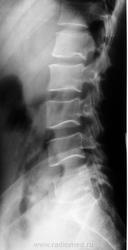

Вопрос об остеохондроме при данном качестве снимков остается вопросом. Раздвигания канала не видно. А вот срединный гребень не отслеживается, структура неоднородная. На боковой проекции патологии крестца не заподозришь. Однако, первый пост удивил. Ни фига себе "начальный остеохондрозик". Не знаю, Любовь С., сопоставляете ли Вы скиалогию с клиникой, но с такой спиной я бы жить не захотел. Один сегмент L5|S1 чего стоит!

Газа в прямой кишке не видно, да и высоковато для прямой кишки, зато в сигме и газ и иное содержимое есть. Добавил ранее обрезанный «низ» боковой проекции. А вот остеохондрома крестца, в боковой проекции действительно должна быть видна, если не кажущаяся.

4. А все мои смущения по поводу данного снимка (рис.1) укладываются не в разрежение структуры дужек L3-4-5 по сравнению с L2 (рис.2); не в псевдопросветление задненижнего сектора тела L5, верхний контур которого образован на самом деле нижним краем основания дужки и выходит за пределы тела (рис. 3); на в кажущееся нарушение структуры крестца, хотя все контуры сегментов, сакрального канала и даже остаточных линий дисков четко отслеживаются (рис. 4), а в наличие грыжевой пролабации типа Поммера каудальной пластины L5, близко расположенной к заднему краю (рис. 5), что при наличии признаков вентральной грыжи диска L5/S1 в сочетании с ретролистезом 1 степени не исключает и заднюю грыжу этого диска.

Если это остеохондрома крестца почему ее не видно на боковой проекции. Как по мне - без МРТ достоверно причины болей не скажешь...

Если бы это был газ в прямой кишке - мы бы его видели в боковой проекции... А там - впечатление о раздвигании кресцового канала в прямой проекции...